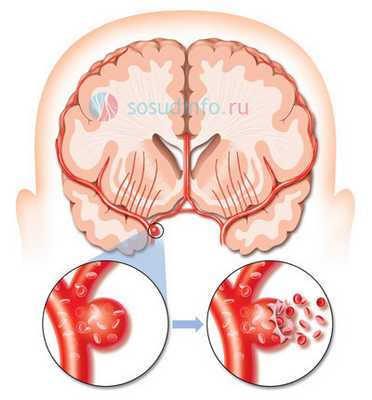

Аневризма сосудов головного мозга - это серьезное заболевание, при котором в стенке артерий головного мозга образуется локальное выпячивание, обусловленное истончением и потерей эластичности пораженного участка стенки. Как показывает статистика, с данной патологией сталкивается около 5% населения. При отсутствии лечения она может осложняться таким жизнеугрожающим состоянием, как разрыв аневризмы. Основным методом лечения этой болезни является хирургическое вмешательство. В данное статье мы поговорим о такой оперативной технике, как клипирование аневризмы сосудов головного мозга.

Аневризма - это патология, которая характеризуется расширением просвета сосуда, выпячиванием сосудистой стенки и формированием аневризматического мешка, обусловленная воздействием факторов врожденного или приобретенного характера. Как правило, аневризма развивается в стенке артерий, а не вен, и чаще всего локализуется в сосудах головного мозга и в аорте.

Из клинических проявлений аневризмы головного мозга можно отметить как незначительные признаки (головные боли, тошнота, общая слабость, нечеткость и помутнение зрения), так и яркую симптоматику, обусловленную не только значительными размерами аневризмы, но и спонтанным ее разрывом с возникновением кровоизлияния в мозг. Опасность аневризмы в том, что человек с ее разрывом и кровоизлиянием может просто мгновенно погибнуть или остаться глубоким инвалидом. Поэтому при диагностированной аневризме сосудов головного мозга принимается решение о ее клипировании или эмболизации.